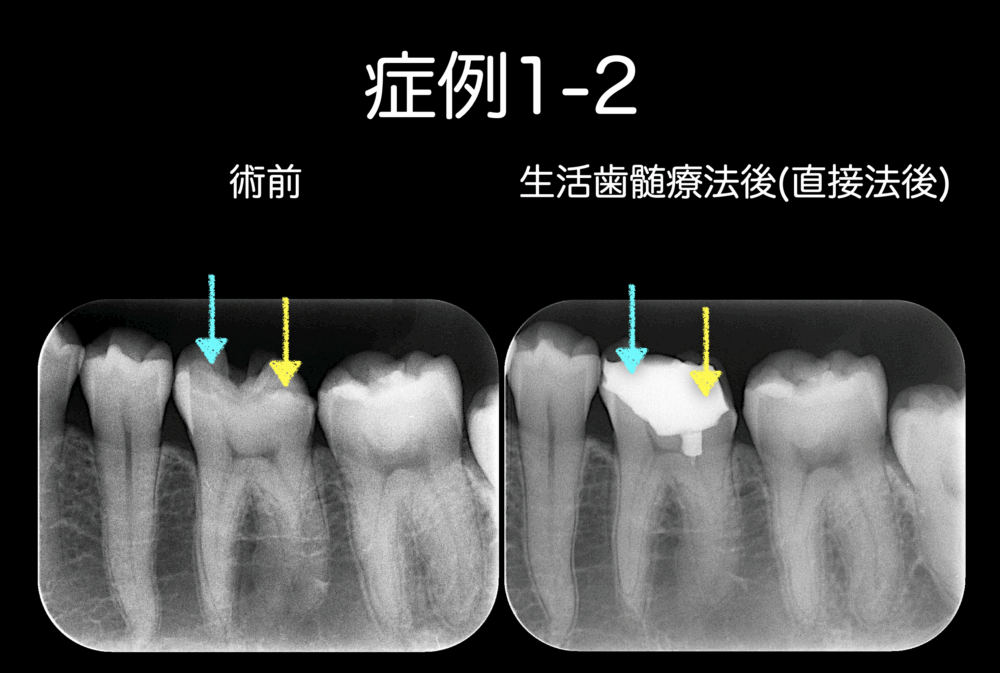

症例1-2は生活歯髄療法前後のレントゲン写真です。

しかし、症例1-1の患者さんがラッキーだったことは、歯髄保存ができるタイミングで虫歯の治療を受けられたことです。

今後も、経過観察を継続していきます。